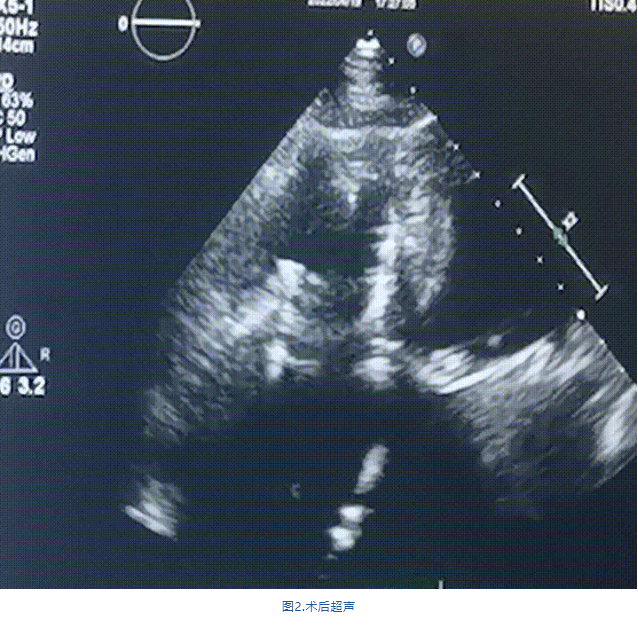

此次手術(shù)在全麻下進行,采用經(jīng)右側(cè)頸靜脈入路。術(shù)中在經(jīng)食道超聲和DSA的指引下多個維度精細調(diào)整輸送器角度,在達到正確位置后,逐步釋放瓣膜錨定裝置和盤片,最終完成瓣膜植入。術(shù)后患者右房壓明顯下降,術(shù)后超聲提示人工三尖瓣同軸性良好,瓣架固定牢靠,無反流和瓣周漏,血壓術(shù)后即刻上升20mmHg左右,手術(shù)后監(jiān)護室順利拔除氣管插管,3天后恢復(fù)良好,予以出院。